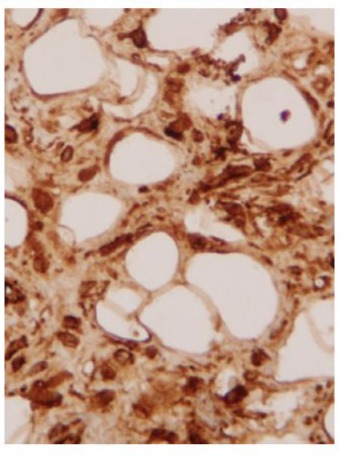

The pathologic specimen was described as well-defined lipomatous formation that stretches its endocardial covering. Tumour area of mature monovacuolar adipocytes with good capsular delimitation of the endocardial strip. Area of spindle-cells and adipocytes, without atypia, and a weft of coarse ropelike bands of collagen fibers. The immunohistochemical study shows immunoreactivity especially in areas for CD-34, positivity for CD-34. Negative for vascular and endocardial endothelial material CD-31. What is the diagnosis? Spindle-cell lipomatous benign tumour of pulmonary valve.

Spindle-cell lipomas. They are a relatively infrequent variant of benign lipomatous soft tissue tumour [79]with good delimitation and encapsulation [80,81]. It is composed of a variable number of typical spindle-cells together with mature adipocytes in a weft of coarse ropelike bands of collagen fibers [80,81]. The appearance of these tumours ranges from those with thin spindlecell tracts that simulate a common lipoma (as is our case), to those with a net predominance of spindle-cells, which give the tumour a fibrous appearance [80]. Possibly some of the tumours previously described as cardiac fibrolipomas correspond to this lipomatous variant [79,80]. Its diagnosis is established when in the immunohistochemical study there is positivity to the immunostaining in spindle-cells for the CD-34 antigen (endothelial marker and hematopoietic progenitors) and negativity for myogenic markers (to exclude myolipomas), as well as the endothelial marker CD-31 for exclude angiolipomas [79,82]. We know a case of spindle-cell lipoma in heart valves [83]. It was a 64-year-old woman with angina and this type of lipoma in the aortic valve. After removing the tumour, the aortic valve had to be replaced [83]. In this case, Rathore and colleagues [83] insist on the discussion on the importance of staining with CD-34, although his paper does not show any CD-34 picture (Figure 5).

Figure 5: Microphotograph (Å~400) of a well-defined lipomatous tumour of mature monovacuolar adipocytes with area of spindle cells and adipocytes, without atypia, and rope-like bands of collagen fibres, where the immunohistochemical study shows immunoreactivity especially in spindle-cell areas positivity for CD-34.